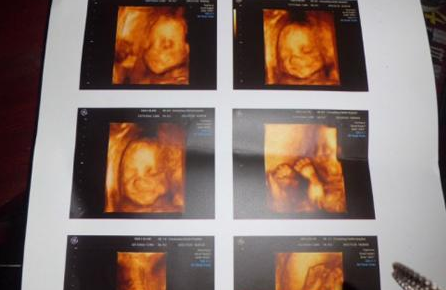

四维彩超:

过去的B超设备只能检查胎儿的生理指标,而四维彩超还能对胎儿的体表进行检查,如唇裂,脊柱裂,大脑、肾、心脏、骨骼发育不良等,以便尽早的进行治疗。生个聪明健康的小宝宝,并且将宝宝的样子和动作制作成照片或DVD,让宝宝拥有最完整的0岁相册,这已经不再是幻想。